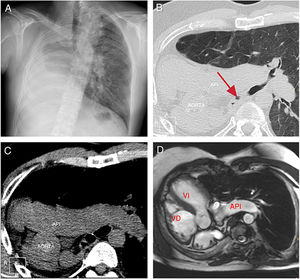

Varón de 37 años diagnosticado al nacimiento de agenesia pulmonar derecha con dextrocardia, intervenido de ductus arteriovenoso persistente a los 8 años, que presentó infecciones respiratorias recurrentes con hiperreactividad bronquial. En las pruebas de imagen (fig. 1) se apreció la agenesia pulmonar derecha junto con hiperinsuflación compensatoria pulmonar izquierda y herniación transmediastínica anterior, así como dextrocardia.

A) Radiografía de tórax, proyección posteroanterior, en la que se objetiva desplazamiento mediastínico y del pulmón izquierdo hacia el hemitórax derecho causado por ausencia del pulmón derecho (agenesia pulmonar). B) Corte axial tomográfico con ventana de parénquima pulmonar. La flecha indica el bronquio principal derecho rudimentario que acaba en fondo de saco. C) Corte axial tomográfico sin contraste intravenoso en el que se aprecia el desplazamiento de estructuras vasculares hacia el hemitórax derecho, así como ausencia de arteria pulmonar derecha. API: arteria pulmonar izquierda. D) Corte axial oblicuo de cine-RM b-FFE. Se observa dextrocardia, dextro-ápex y la ausencia completa de parénquima pulmonar derecho. VD: ventrículo; VI: ventrículo izquierdo.